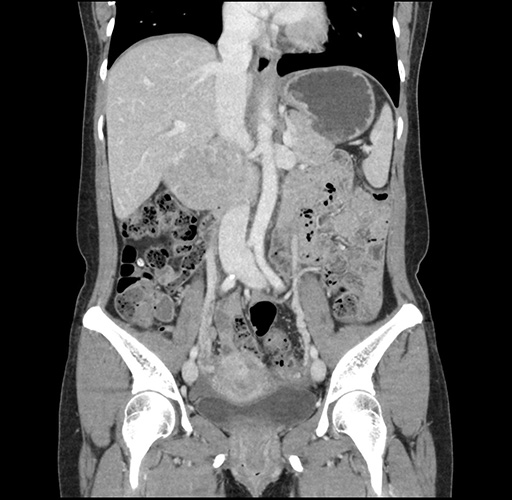

Imaging Analysis

Look through the patient's CT scan to identify any areas of concern for the necessary procedure.

Based on your CT findings, which issue(s) would give reason for "planned slowing down moment(s)" in this case?